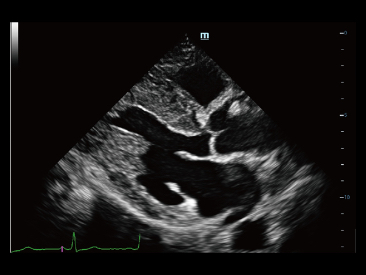

Since the company was founded, Mindray has been continuously exploring new ways to improve diagnostic confidence. Powered by the most revolutionary ZONE Sonography? Technology, Resona 7ŌĆÖs new ZST+ platform brings ultrasound image quality to a higher level by zone acquisition and channel data processing.

As well as the premium level image quality, Resona 7 also enhances clinical research capabilities with the revolutionary V Flow for vascular hemodynamic evaluation, and the most intelligent plane acquisition from 3D datasets for fetal CNS diagnosis. Combining the most intuitive gesture-based multi-touch operation and all the essential clinical features, Resona 7 is truly leading new waves in ultrasound innovation.